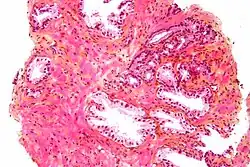

Micrograph showing inflamed prostate (H&E stain) with large amount of darker cells (leukocytes); area without inflammation seen on the left

Prostatitis is inflammation of the prostate gland. It can be caused by infection with bacteria, or other noninfective causes. Inflammation of the prostate can cause painful urination or ejaculation, groin pain, difficulty passing urine, or constitutional symptoms such as fever or tiredness.[28] When inflamed, the prostate becomes enlarged and is tender when touched during digital rectal examination. The bacteria responsible for the infection may be detected by a urine culture.[28]

Acute prostatitis and chronic bacterial prostatitis are treated with antibiotics.[28] Chronic non-bacterial prostatitis, or male chronic pelvic pain syndrome is treated by a large variety of modalities including the medications alpha blockers, non-steroidal anti-inflammatories and amitriptyline,[28] antihistamines, and other anxiolytics.[29] Other treatments that are not medications may include physical therapy,[30] psychotherapy, nerve modulators, and surgery. More recently, a combination of trigger point and psychological therapy has proved effective for category III prostatitis as well.[29]